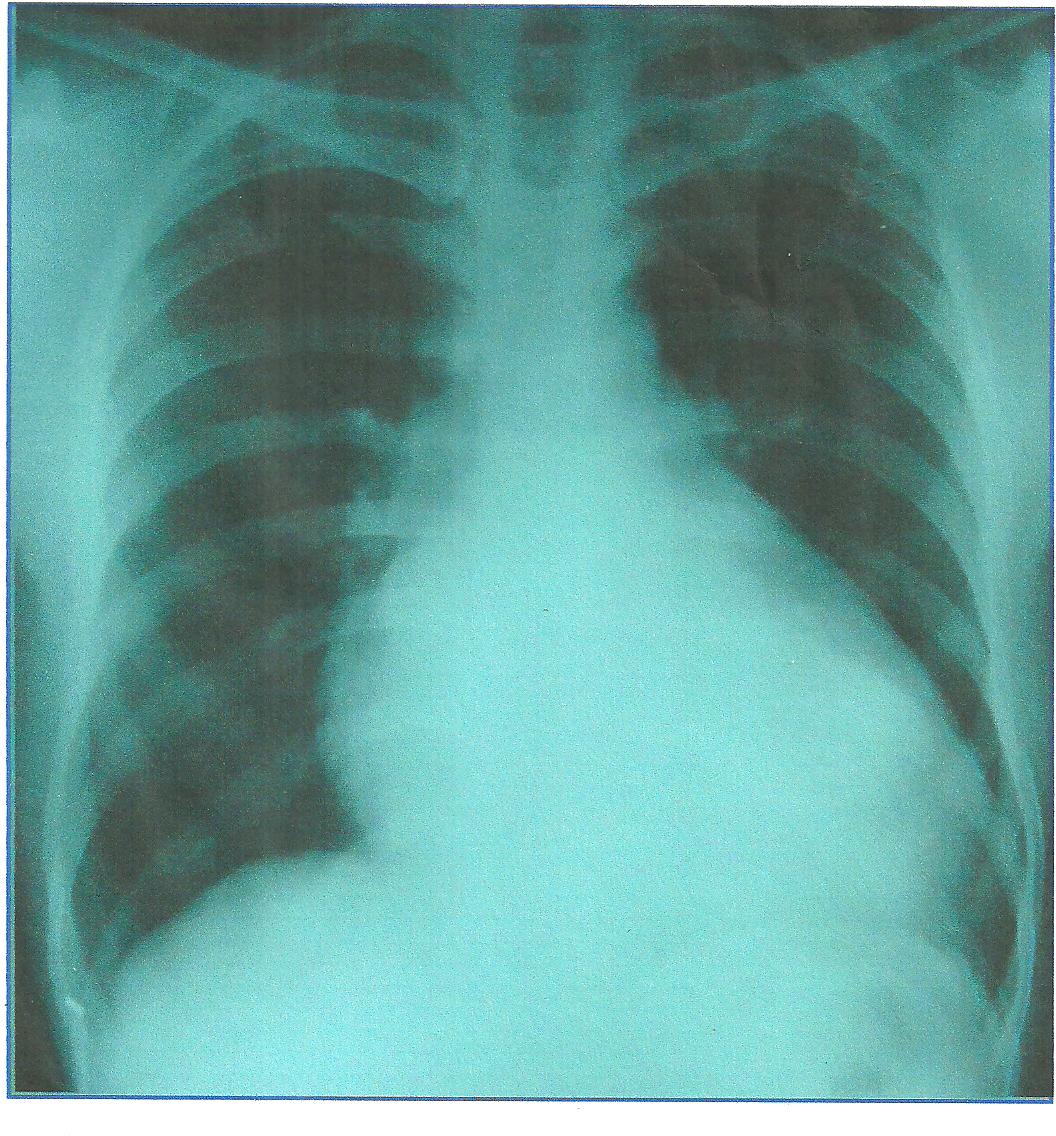

Chest X ray –

Cardiomegaly

§Lung fields – within normal limit